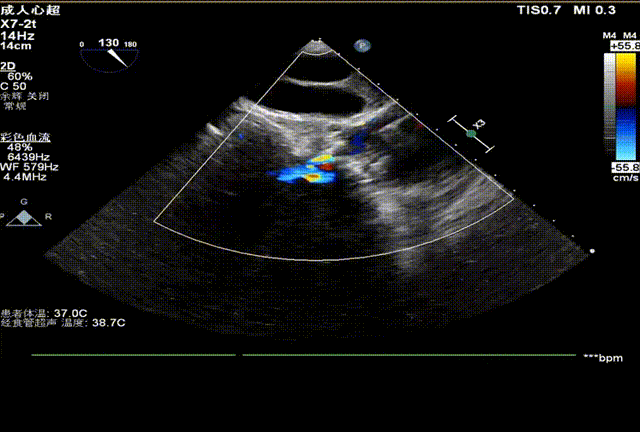

心脏彩超

峰值流速:4.2m/s

最高跨瓣压差:69mmHg

平均跨瓣压差:43mmHg

左室射血分数EF值: 26%

左室舒张末期内径(LVD):6.13 cm

超声提示:主动脉重度狭窄伴轻-中度关闭不全

二尖瓣中-重度、三尖瓣轻-中度关闭不全

心功能不全(限制型)

轻度肺动脉高压

即刻超声评估示瓣周漏显著降低